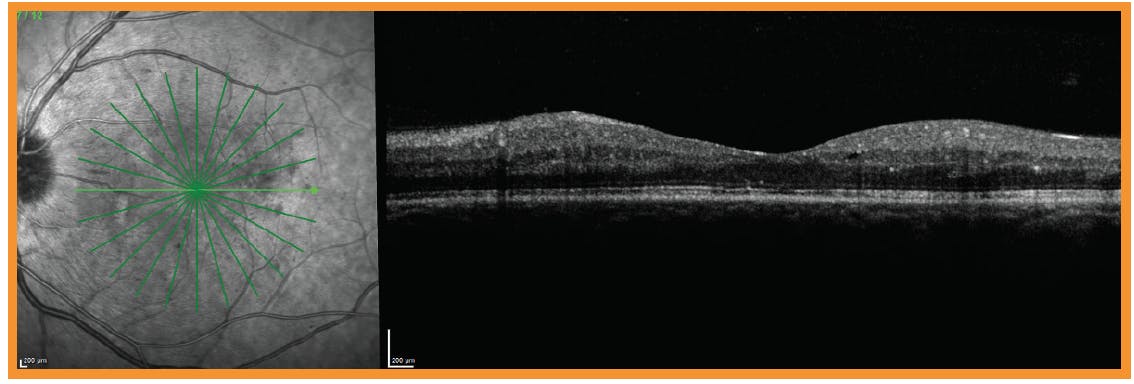

CASE 2: Is it Clinically Significant DME?

Dr. Wykoff: Our next case is a patient I saw in December 2019 who was 20/25 OU. The OCT in the right eye shows a small intraretinal cyst in the cross-sectional image through the fovea with some mild thickening just superior/temporal to the fovea (Figure 2). Do you consider this clinically meaningful DME? The color fundus photograph (Figure 2) shows mild intraretinal hemorrhages and scattered cotton wool spots. In my opinion, this patient is in a gray zone for a referral. Many of our optometry colleagues would continue to monitor this patient because the patient is asymptomatic, but others would refer for retinal evaluation. How would you manage this patient?

Dr. Miller: I think it depends on their A1C blood sugar control, and how long ago the patient was diagnosed. I’d watch this patient closely for 6 months and refer if there are any changes. The question is, how quickly will this patient progress? Sometimes diabetic eye disease advances rapidly, but other times it takes years to develop. We need to be ahead of it rather than behind it.

Dr. Wykoff: Figure 3 shows the fellow eye in the same patient. On the OCT, we see a central cyst and a mild swelling. How do you define this? While there is definitely center-involving DME and vision is not normal, the vision is relatively preserved. How would you consider managing this patient? Where should this patient be seen in follow-up?

Dr. Ho: I’d follow this patient with an allied eye care provider, but I’d want to see them initially over time. We have new information from the literature that says we don’t have to jump to treat patients with good vision and some mild structural edema. The Diabetic Retinopathy Clinical Research Network (DRCR.net) Protocol V trial recommends observation as a strategy to consider in patients with center-involved DME and good central vision.35

Protocol V was conducted at 91 sites in the United States and Canada between November 2013 and September 2016. The study enrolled more than 700 patients with center-involved DME and a visual acuity (VA) of 20/25 or better who were randomly assigned to either aflibercept (n = 226), laser (n = 240), or observation (n = 236). The rate of vision loss of 5 or more letters did not significantly differ between the three groups at 2 years.35 The average VA was 20/20 2 years later, just as it was at baseline. Their vision doesn’t always decline and sometimes the edema improves on its own.

Dr. Wykoff: I initially observed this patient. I brought this patient back about 6 weeks later, and vision in the left eye had deteriorated to 20/30 and they were now symptomatic. We started treatment. After three monthly anti-VEGF injections, the fovea normalized, and the edema resolved. I’ve stopped injections and have moved to observation since then.

Dr. Ferrucci: As an optometrist, if I have a patient with center-involved DME, even if their vision is good, I usually recommend a referral just to hear the retinal specialist’s opinion.

Dr. Miller: I also like to refer for any disease that is center-involved. Even if the decision is to observe, I’d rather the patient be observed by a retinal specialist. If the patient can establish a relationship with a retinal specialist they trust early on, it makes any treatments down the road easier to take on.

Dr. Gupta: I agree. I tend to observe these patients, if their VA is 20/20 or 20/25 and have well-controlled disease. I still like to see these patients sooner rather than later (ie, not waiting until their vision drops), because I find that its helpful to have met them and built some rapport before they reach the point where they need interventions. The first injection can be a huge psychological burden for patients. For some, the anxiety is worse than the injection itself. It’s nice to have met them and had that first conversation about what could happen if their disease progresses to and get them prepared and establish a relationship before such interventions are necessary.